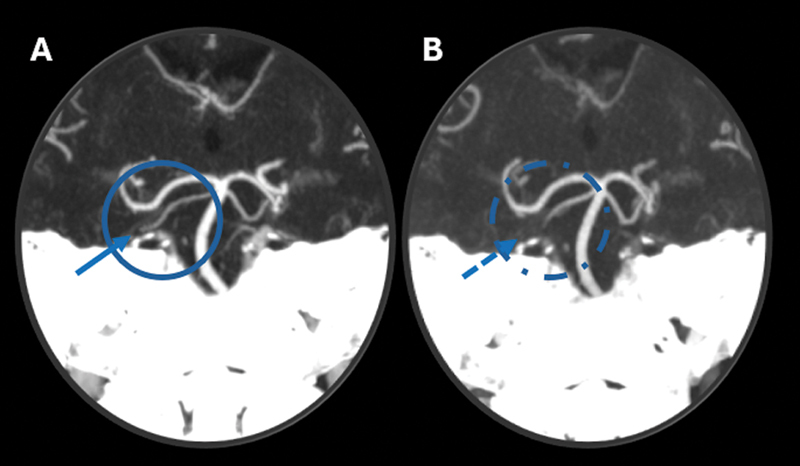

Unmasking vertebral artery stump syndrome in recurrent posterior strokes treated with endovascular therapy.